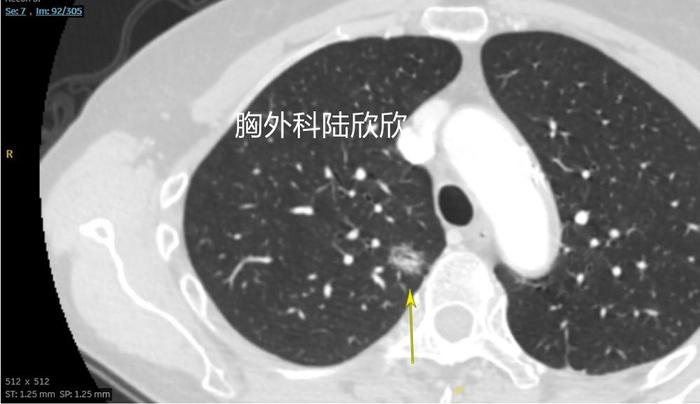

上图,薄层CT的92层面,可见右上肺结节的最上边基本上是磨玻璃成分,看起来像是一个鸟巢